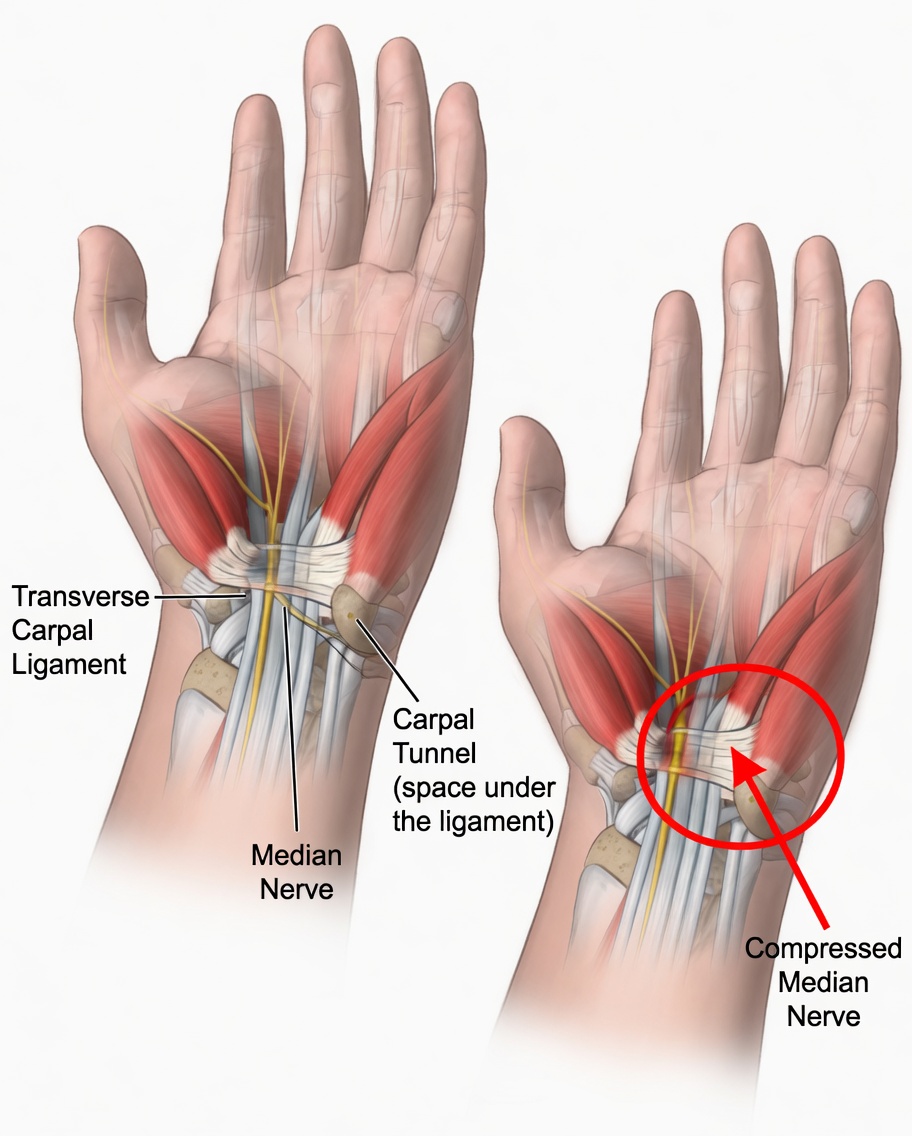

What Is Carpal Tunnel Syndrome?

The carpal tunnel is a narrow passageway in the wrist through which the median nerve runs. When this nerve is compressed due to swelling, inflammation, or constant pressure, it can lead to discomfort, numbness, weakness, and pain in the hand and wrist.